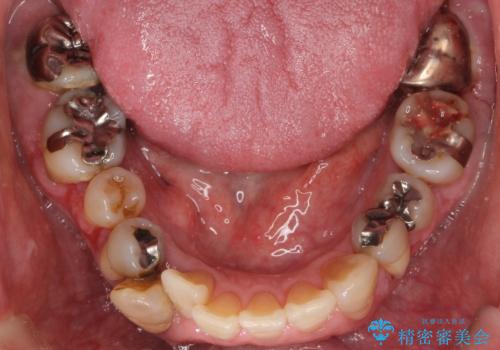

- 全顎的な重度歯周病の患者様です。

埋伏していた親知らず、保存不可能な左下の一番奥の歯(左下7)は抜歯しました。

- ¥670,000 (再生療法、骨外科処置、仮歯×3本、土台×1本、被せ物×3本)費用は治療当時の料金となります